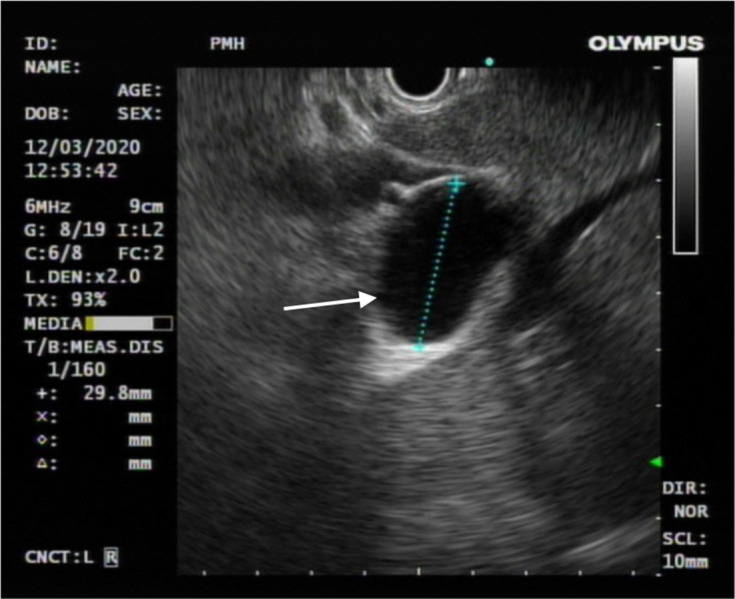

Methods: We report a case of cystic hepatic lesion near the confluence of bilateral intrahepatic ducts. MRCP shows direct anatomical communication between the lesion and the biliary tract, raising suspicion of a CC. Endoscopic ultrasound shows no communication between the lesion and biliary system. 99mTc-hepatic iminodiacetic acid scintigraphy (hepatobiliary scintigraphy) was subsequently performed, showing no tracer uptake in the concerned cystic hepatic lesion despite visualisation of gallbladder and transit of tracer into the intestine. Overall scintigraphic findings speak against a CC.